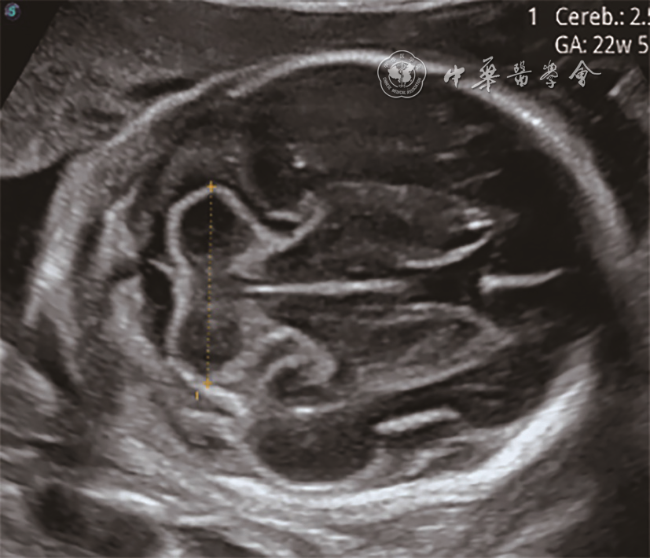

3. 磁共振辅助诊断4例,其中3例胎儿左侧小脑发育不全(图67),1例右侧小脑发育不全。

图6 孕25周胎儿(例5)产前颅脑轴位MRI T2WI 显示左侧小脑半球明显变小

图7 孕23周胎儿(例4)产前颅脑轴位MRI T2WI图像(图a);孕22周胎儿(例6)产前颅脑冠状位MRI T2WI图像(图b)均显示一侧小脑半球明显变小